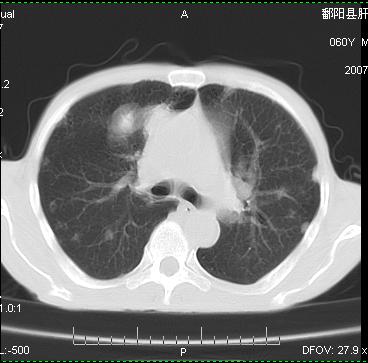

两肺示有散在大小不等类园形边缘不整密增高影.

两肺及胸膜多发性转移瘤。

两肺及胸膜多发性转移瘤。纵隔淋巴结转移.

双侧胸壁见多发结节软组织密度灶,两肺内见广泛结节状、面团样影,两肺及胸膜多发性转移瘤。支持

根据:病变确实是多发,但大部分边缘不光滑,欠规整,密度不均匀。也就是说“大部分病灶不是典型转移瘤的表现”。转移瘤可以不典型,但如此大部分不典型,却是很少见的。结合发烧病史,考虑肺多发小脓肿或其他炎性病变,如霉菌等感染!建议痰培养,抗炎治疗后复查!

从病人年龄及肺内表现首先考虑转移瘤,但病人以咳嗽发热胸痛为首发症状还要考虑血行播散型肺脓肿及白血病非内表现等,结合实验室检查有鉴别意义。